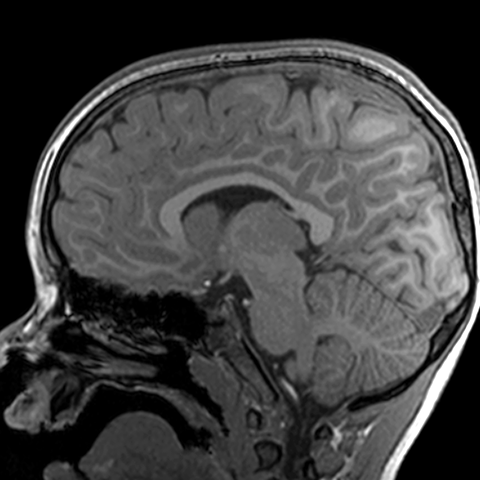

Sagittal image of skull and brain (T1-weighted MRI) [7 of 7]